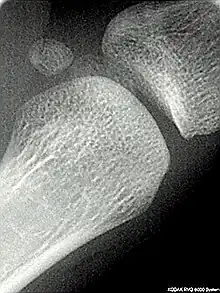

Les os sésamoïdes (du grec, sêsamoeides : qui ressemble au sésame) sont de petits os que l’on trouve principalement près des articulations et dans l’épaisseur de tendons[1]. La formation des os sésamoïdes est différente de celle des autres os, puisque ce sont des vestiges de ligaments calcifiés, c’est pourquoi ils ne sont pas tous considérés comme partie intégrante du squelette humain.

Os sésamoïdes constants

- la patella est le plus gros os sésamoïde[2], il est situé dans le tendon inférieur du muscle quadriceps fémoral, il est considéré comme un os à part entière,

- Le pisiforme est un os sésamoïde dans le tendon du muscle fléchisseur ulnaire du carpe[3] qui commence à s'ossifier chez les enfants entre 9 et 12 ans[4], il est considéré comme un os du carpe,

- au niveau de la main, deux os sésamoïdes se trouvent généralement dans les parties distales du premier métacarpien dans les tendons du muscle adducteur du pouce et du muscle court fléchisseur du pouce du pouce et couramment il existe un os sésamoïde dans les parties distales du deuxième métacarpien,

- au niveau du pied, deux os sésamoïdes se trouvent dans les parties distales du premier métatarsien dans le tendon du muscle court fléchisseur de l'hallux[5], chez certaines personnes, il n'y a qu'un seul os sésamoïde.